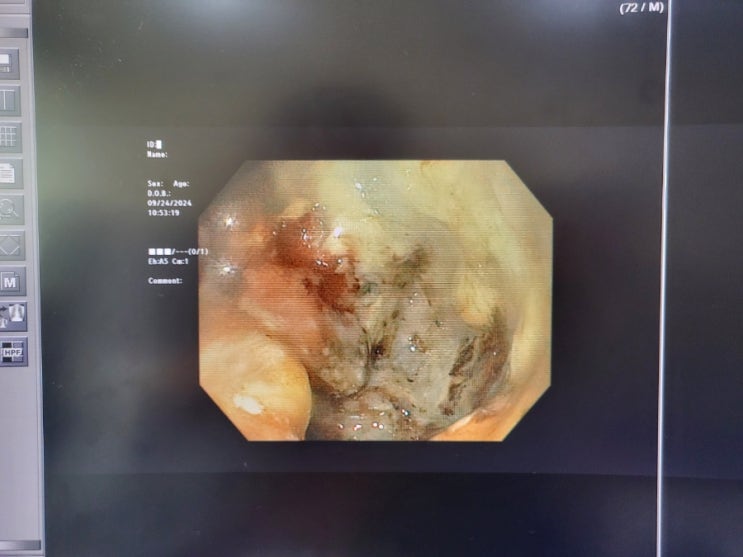

이 내시경 사진은 제 사진이 아닙니다. 당신의 사진도 아니지요. 오늘 아무 일도 없었다면 당신은 행운입니...